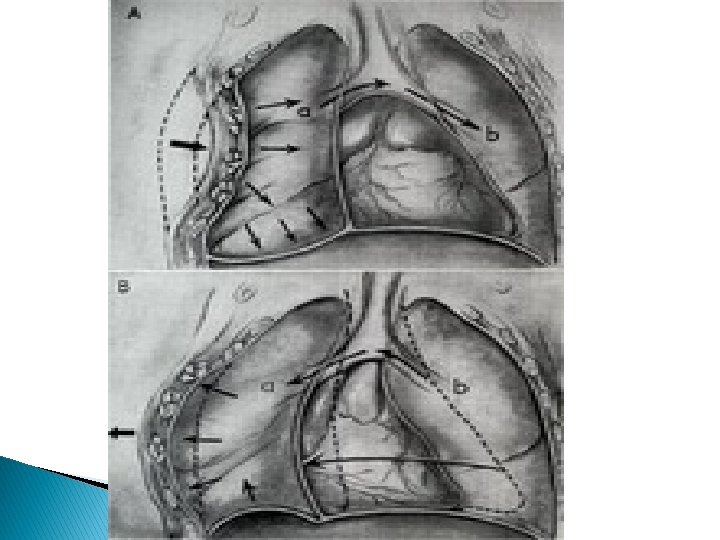

Flail chest � Flail chest is traditionally described as the paradoxical movement of a segment of chest wall caused by fractures of 3 or more ribs anteriorly and posteriorly within each rib. � Variations include posterior flail segments, and flail including the sternum with ribs on both sides of the thoracic cage fractured. � Severe blunt trauma